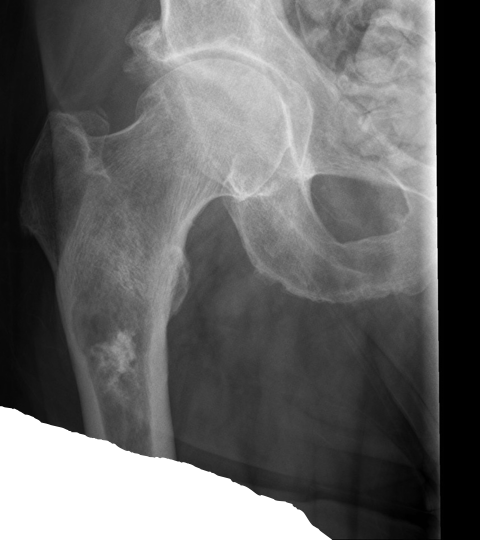

68-year-old man presents to his primary care physician for left leg pain.

His pain has been progressively worsening over the course of a month and is present at night.

Physical examination demonstrates impaired left lower extremity weakness limited by pain.

A radiograph of the left hip and femur demonstrates lytic lesions and intralesional calcifications.

Chondrosarcoma

Radiograph shows popcorn leisions!!!